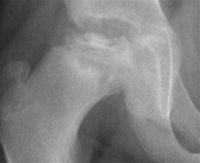

- Behandling er oftest konservativt i starten. Barnet skal aflaste, og der skal udføres hjemmetræning og fysioterapi for at bibeholde bevægelighed i hoften. Målet er såkaldt 'containment', dvs. hoftehovedet centreres i acetabularskålen

- Barnet følges løbende klinisk og radiologisk, og hvis den ønskede udvikling i hoftehovedet og 'containment' i hofteleddet ikke opnås, så behandles kirurgisk